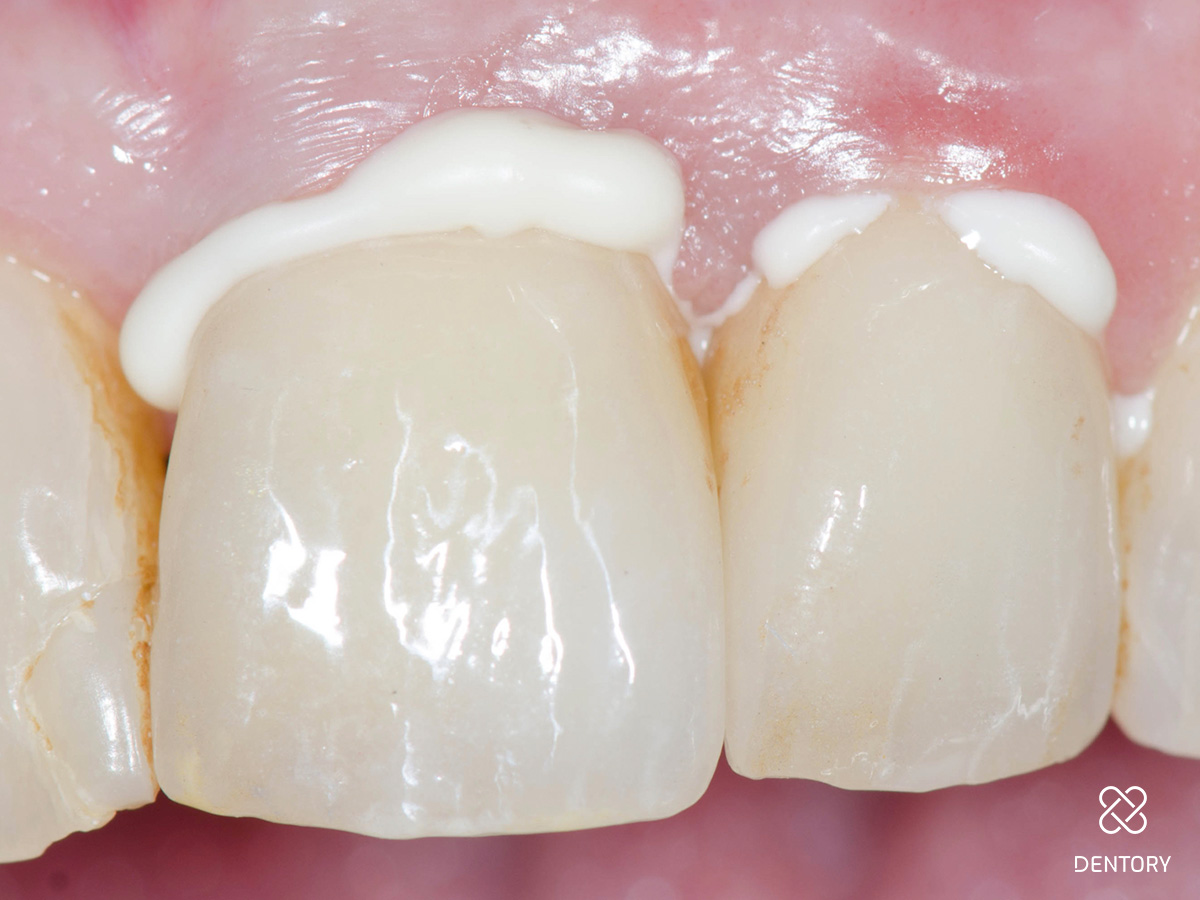

Abbildung 3

Kronenentfernung: Die Zähne waren wurzelkanalbehandelt und mit einem Stift versorgt. Das Bild zeigt die Situation nach Abnahme der Krone und Präparation der Stümpfe.